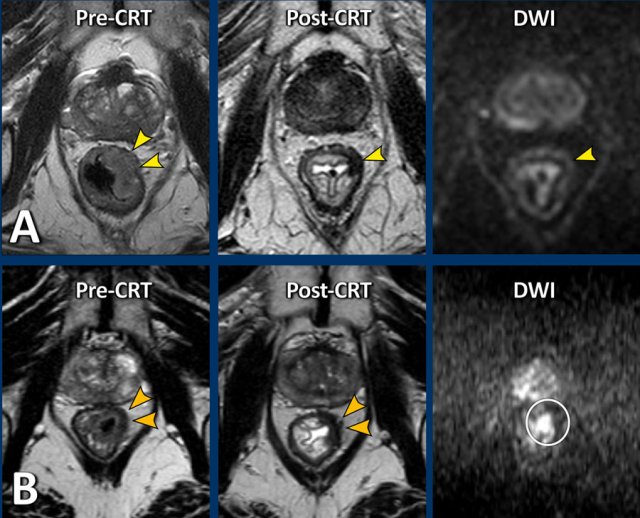

Diffusion-weighted imaging

DWI

highlights tissue with a high cellular density in which the extracellular

movement of water is “restricted”.

DWI has been shown to be a useful adjunct to T2-weighted MRI

to diagnose the presence of viable residual tumor within the fibrotically

changed tumor bed after CRT [reference].

In case of residual tumor, a high signal can typically be

observed at the inner margin of the fibrosis on high b-value diffusion-weighted

images, with a corresponding low signal on the ADC map.

Images

The

images show the primary staging and restaging T2-weighted images after

chemoradiotherapy with predominant fibrosis with minor signal heterogeneity

(TRG 3).

The corresponding restaging DWI shows a focal area of high

signal at the inner margin of the fibrosis with corresponding low signal on the

ADC map, indicating restricted diffusion.

This

was confirmed to be a small tumor remnant (ypT2) at histopathology.

Here are two more examples of patients with very similar semicircular tumors pre- and post-CRT.

On the T2W-images post-CRT both patients show some fibrotic wall thickening in the radiated area, but no obvious solid tumor remnant (yellow arrowheads).

On DWI, patient A shows no mass-like diffusion restriction. There is only some shine through of fluid signal in the lumen.

In patient B there is focal restricted diffusion at the site of the fibrosis.

Patient A was confirmed to be a complete responder at endoscopy and went into a wait-and-see program.

Patient B underwent resection which confirmed a ypT2 tumor remnant.